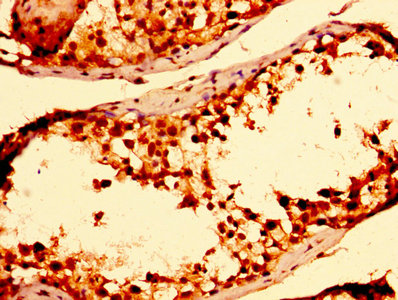

• IHC image of CSB-PA02814A0Rb diluted at 1:300 and staining in paraffin-embedded human testis tissue performed on a Leica BondTM system. After dewaxing and hydration, antigen retrieval was mediated by high pressure in a citrate buffer (pH 6.0). Section was blocked with 10% normal goat serum 30min at RT. Then primary antibody (1% BSA) was incubated at 4°C overnight. The primary is detected by a biotinylated secondary antibody and visualized using an HRP conjugated SP system.